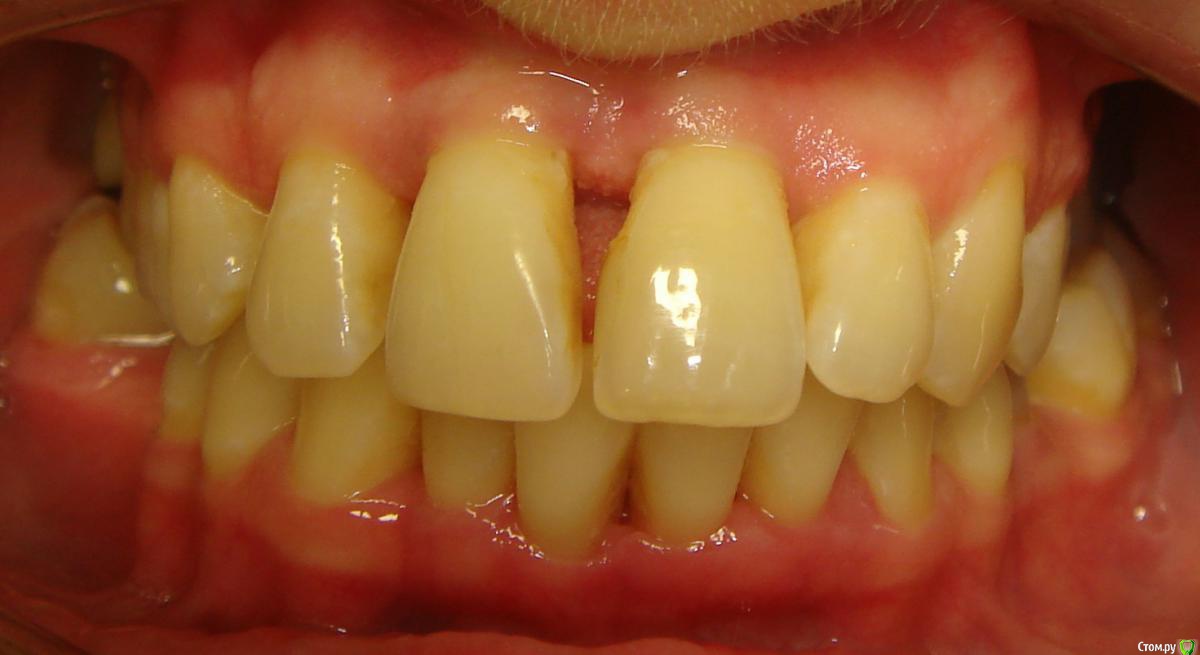

Opdihatop Опубликовано 9 мая, 2016 Поделиться Опубликовано 9 мая, 2016 (изменено) Здравствуйте, коллеги! Хотел бы представить вашему вниманию вот такой вот случай и спросить совета. В принципе, по окклюзии ничего особенного по лечению нет, но вот проблемы с пародонтом (на КТ по кости все заметно хуже, чем на орто), делают невозможным все, продуманные мной варианты. Может у кого-то было что-то подобное? Может поделитесь советом, а то помочь человеку надо, а я в тупике. Буду заранее очень благодарен за помощь! Изменено 9 мая, 2016 пользователем Opdihatop Ссылка на комментарий

Yana guapa Опубликовано 12 мая, 2016 Поделиться Опубликовано 12 мая, 2016 показаний к сарпе здесь нет. дать разобщение и перебросить боковые зубы кросс тягой. внизу бы не удаляла. на самолигах итак места достаточно будет. ну максимум стриппинг. были такие пациенты, что думала зубы с лигатурами вылетят ... но ничего! к концу лечения укрепились даже! все на месте! просто у таких пациентов еще нежнее надо 1 Ссылка на комментарий

CRAZYDUCK Опубликовано 13 мая, 2016 Поделиться Опубликовано 13 мая, 2016 плюс Яне и m.d.n.Попов СА на своих семинарах показывал много случаев подобных , лечил самолигирующимися , начинал с малых дуг 12 или 13, только просил кт и заключение пародонтолога , что пациент в стадии ремиссии. Ссылка на комментарий